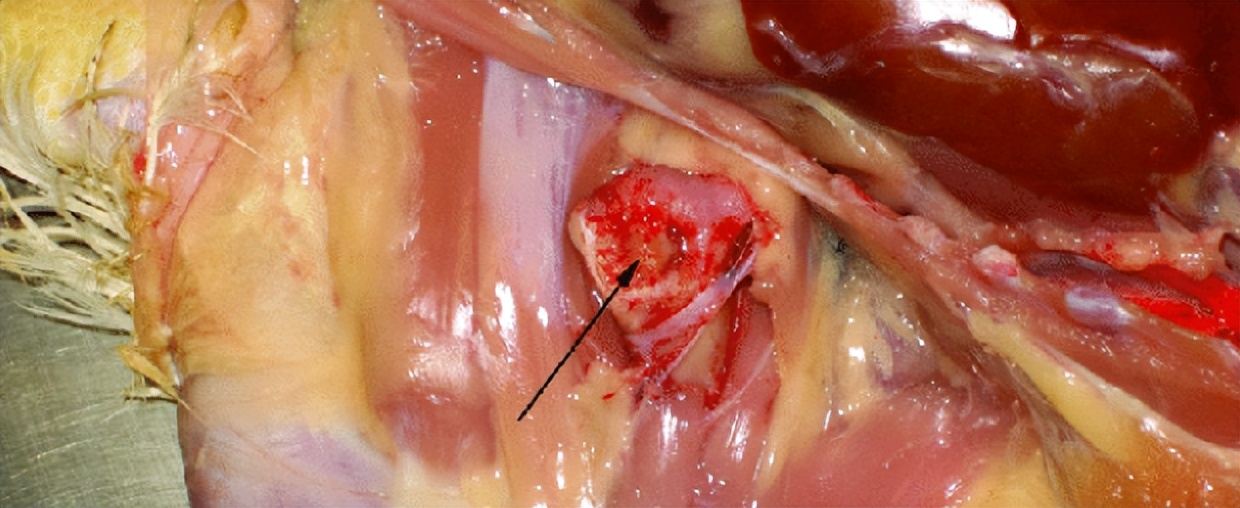

骨髓炎

股骨近端的生长板患细菌性骨髓炎导致易碎,且常规剖检时关节脱臼可能会致股骨颈破裂。在骺软骨板和干骺部可见骨髓炎病灶。此病发生在菌血症之后,在骨形成一个感染性病灶。从病变部位最常分离到埃希氏大肠杆菌和葡萄球菌, 不常分离到的病菌有沙门氏菌、耶尔森氏鼠疫杆菌、链球菌、巴斯德菌以及亚利桑那菌 。